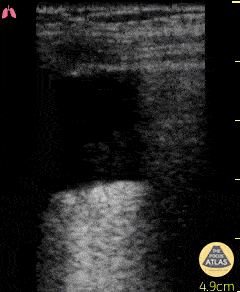

This clip, demonstrating a hydropoint, was taken in a 74 year old M with chest trauma after a fall from 3 meters. A hydropoint shows the air/fluid interface which is suggestive for hemato/hydro/pyo-pneumothorax. It is another sign for diagnosing a pneumothorax described by Volpicelli et al. Critical Ultrasound Journal. 2013 Dr. Van Roosmalen